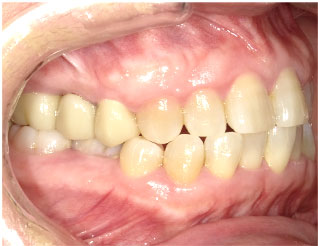

- ブリッジ 症例写真 B-0113FZC8本 女性モニターの方です。

Before

After詳細はコチラ

フルジルコニアによるブリッジ治療の症例

- No. B-0113

施術 FZC8本 - コメント

この方は古い差し歯の黄ばみを治したいとご来院されました。 奥歯に欠損もありましたので、前歯はジルコニアセラミック、奥はジルコニアブリッジで治しました。 1回の治療で前歯も奥歯も同時進行で治療します。 1回目の治療時に仮歯を入れますので、すぐに見た目が気にならなくなります。 治療回数は5回でした。